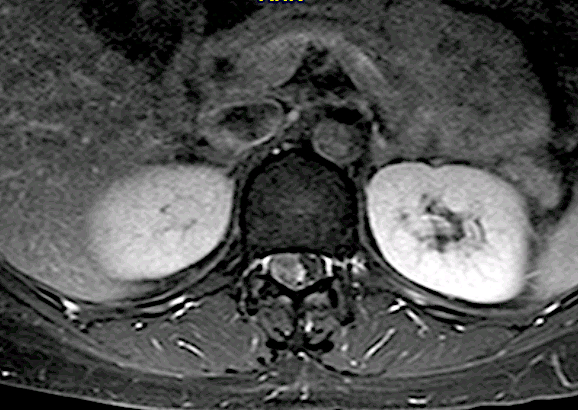

Paciente 73 años con lumbalgia inespecífica asociada a disestesias ocasionales en L3 derecha.

En este caso, a diferencia del caso «Schwannoma lumbar (L3, “raíz no elocuente” ), se optó por un abordaje longitudinal medial con laminotomía + laminoplastia L1 y resección parcial lámina Th12.

Control RM postoperatorio con exéresis completa. Obsérvese el trazo de la laminotomía con la integridad de grupos musculares.